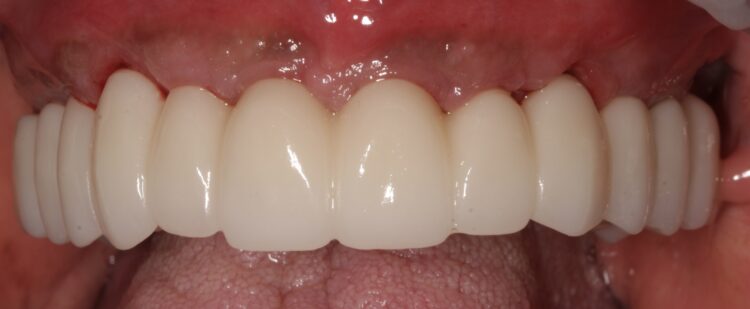

Based on the digital design and copying the approved provisional prosthesis, a zirconia overlay was milled. The overlaying zirconia superstructure was digitally designed to fit the metal substructure, accomplish a flawless finish line, avoid any undercuts and verify the path of insertion, thus facilitating the bonding procedures. The zirconia superstructure was bonded with the titanium substructure using a self-curing luting composite. The final polished screw-retained prosthesis was delivered and torqued to 30Ncm and the radiographic assessment was executed.

After the follow up appointments at one and four weeks, the patient was scheduled for periodic maintenance every three months. The retrievability of the final screw-retained zirconia-titanium supported prosthesis allowed management of the interface over time. At the one-year review, further growth and maturation of the soft tissue as well as the health of the keratinised peri-implant tissues were evident, without signs of bleeding on probing.

The patient was thrilled with the final outcomes achieved in this case, as was I. The failing dentition was replaced by a fixed, long-term – with patient oral hygiene compliance – and cleansable solution, which will restore the patient’s quality of life.

Particularly in FP1 cases where a correct emergence profile has to be formed through the implant-supported immediate temporary prosthesis, a digital treatment plan and guided surgery offer a comprehensive workflow to achieve predictable high-end prosthetic results that mimic the natural dentition.

The translucent zirconia supported by titanium framework fulfils the aesthetic and mechanical requirements of an FP1 full arch prosthesis, while minimising the risk of fracture by providing a rigid yet passive joint to support the implants.[vi] The zirconia and titanium transmucosal surface characteristics (otherwise known as biocompatibility) create a highly polished interface for high cell adhesion and optimised gingival architecture.